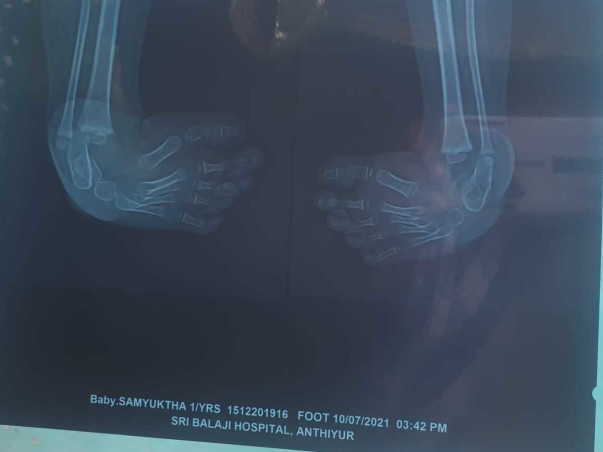

We are belongs to daily wege family and she had heart disease initaily, that was treated with our extreme effort. And now she is ready for clubfoot treatment. For that OPERATION to be done for both legs and we don't have money to do this operation. So please help us. Your small contribution will also save my daughter health. Please help Samyuktha. Thank you.